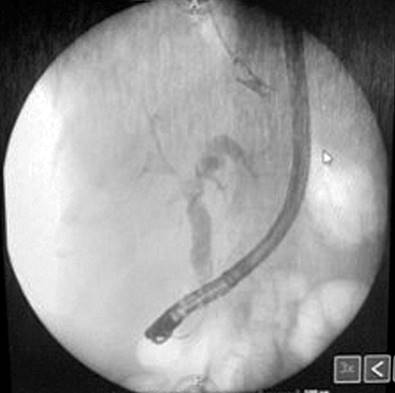

On her last visit, the patient went to the emergency room with the symptoms described above, leukocytosis, increased bilirubin, cholestasis enzymes (Table 1), and jaundice in the sclera and mucous membranes. The diagnosis of cholangitis was assessed, for which an MRE cholangiography was performed, showing new findings in favor of multiple intrahepatic cystic lesions with an annular enhancement of the contrast medium and dilation of the intrahepatic and extrahepatic bile ducts. These findings were consistent with Caroli’s disease. An intervention with endoscopic retrograde cholangiopancreatography (ERCP) was made, in which a sphincterotomy was performed before cannulation. The discharge of choledocholithiasis and seropurulent content consistent with cholangitis was observed, later placing a 10 Fr/9 cm plastic prosthesis (Figure 3).

Figure 3 ERCP showing seropurulent content consistent with cholangitis. Source: Patient’s medical record.